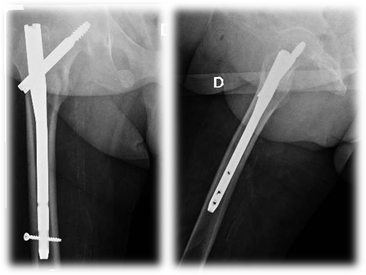

Tornillo Deslizante de Cadera (TDC) (Figura 2)

Anestesia intratecal. Paciente en decúbito dorsal sobre mesa de tracción. Reducción cerrada bajo visión de intensificador de imágenes. Incisión centrada sobre la línea del eje femoral lateral a nivel del trocánter menor, y extensión de 10 cm hacia distal. Se aborda el tensor de la fascia lata y luego subvasto lateral, retrayendo la masa muscular móvil anteriormente. Se introduce clavija guía a lo largo del eje del cuello femoral hacia el hueso subcondral de la cabeza, hasta obtener una distancia punta-ápex de 2,5 cm (sumatoria de frente y perfil). Luego se coloca una segunda clavija kirschner de forma antirrotatoria paralela a la primera. Fresado para el tornillo deslizante. Se inserta cañón. Se coloca la placa con sus tornillos. Compresión del foco de fractura. Cierre por planos.

Clavo cefalomedular (CCM) (Figura 3)

Anestesia intratecal. Paciente en decúbito dorsal sobre mesa de tracción. Reducción cerrada bajo visión de intensificador de imágenes. Abordaje 5 cm proximal al trocánter mayor con 10-15º hacia posterior. Se realiza fasciotomía. Se pasa clavija guía iniciadora a 6° del eje femoral, luego punta cuadrada. Se fresa la entrada. Se coloca clavo cefalomedular y se inserta la guía para el cañón. Se pasa el escariador y luego se coloca el cañón definitivo y el cerrojo distal. Compresión del foco de fractura. Cierre por planos.

Figura 2- Tornillo Deslizante de Cadera (TDC)

Figura 3- Clavo cefalomedular (CCM)

Figura 2

Figura 3